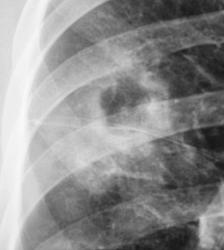

Пациент взят на контроль после флюорографии. Произвели только обзорный снимок.

Прошло 3 месяца, и сегодня, фтизиатр прислал на «контроль», взятого на заметку.

Стало ясно, что линейная томография в данном случае не повредит.

См. Стрелки. Целесообразно сделать задний снимок. С уважением Nikolas

Да, я посмотрел стрелочки, я полностью согласен. Но у меня граз цеплялся справа...

Формально фтизиатры поставят диагноз инфильтративный туберкулез S6 правого легкого, фаза распада. Но, я не зря спросил про возраст больного. У молодых людей нижнедолевой туберкулез особенно в 6 сегменте часто связан с поражением внутригрудных лимфатических узлов. Пути распространения инфекции лимфобронхогенное. Подтверждением этого является обнаружение при бронхоскопии различных форм активного туберкулеза (инфильтративный, язвенный и лимфобронхиальный свищ). При бронхоскопии у больного могут найдут специфическое поржение бронхов. Лимфогенный путь распространения напоминает раковый лимфангиит . О лимфогенном распространении инфекции указывает прединфильтратная сетка, которую хорошо видно на рентгенограммах. О поражении лимфатических бронхопульмональных узлов свидетельствует вовлечение в процесс плевральных листков в виде воспалительного уплотнения междолевой плевры, а также наклонность к раннему образованию распада. Известно,что у взрослых трудно выявить изменения со стороны ВГЛУ, так как они не часто достигают той величины, как у детей. Умеренно выраженное увеличение бронхопульмональных л/у на КТ диагностируется только при контрастировании. Таким образом, предварительный патогенетический диагноз звучал бы так : туберкулез внутригрудных лимфатических узлов бронхопульмональной группы справа, осложненный бронхолегочным поражением в S6 с распадом. Необходимо построить патогенетический диагноз, так как специфические изменения в лимфатических узлах требуют более длительного лечения. Такова моя точка зрения на диагноз у представленного пациента. С уважением Ваш NIkolas